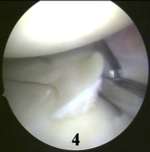

Sau đó dùng kéo cắt dần ở trước mảnh sụn chêm bong ra.(4)